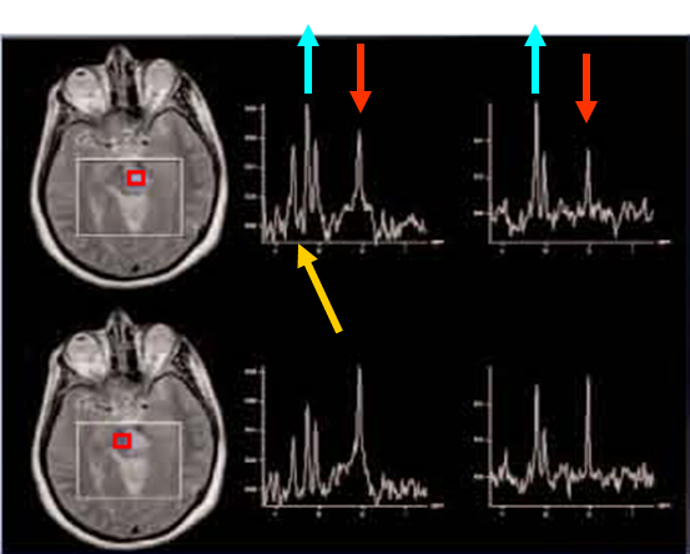

Magnetic Resonance (MR) Spectroscopy

Magnetic resonance (MR) spectroscopy is a noninvasive diagnostic test for measuring biochemical changes in the brain, especially the presence of tumors. MR spectroscopy compares the chemical composition of normal brain tissue with abnormal tumor tissue.

Click images for larger view and description